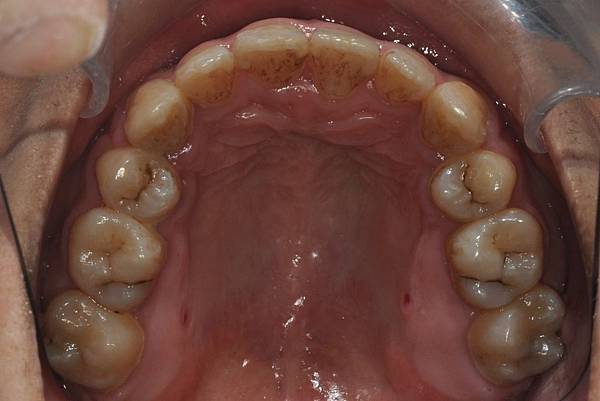

網紅林進藉由矯正改善臉型達到整形效果

拔牙合併微骨釘

本來就很愛笑的林進,藉由“

”

將前牙後退嘴脣後縮,並藉由齒列上壓作下顎逆時針旋轉,達到接近整形墊下巴的效果!!

治療前/治療後

-以上案例由林昇進醫師提供